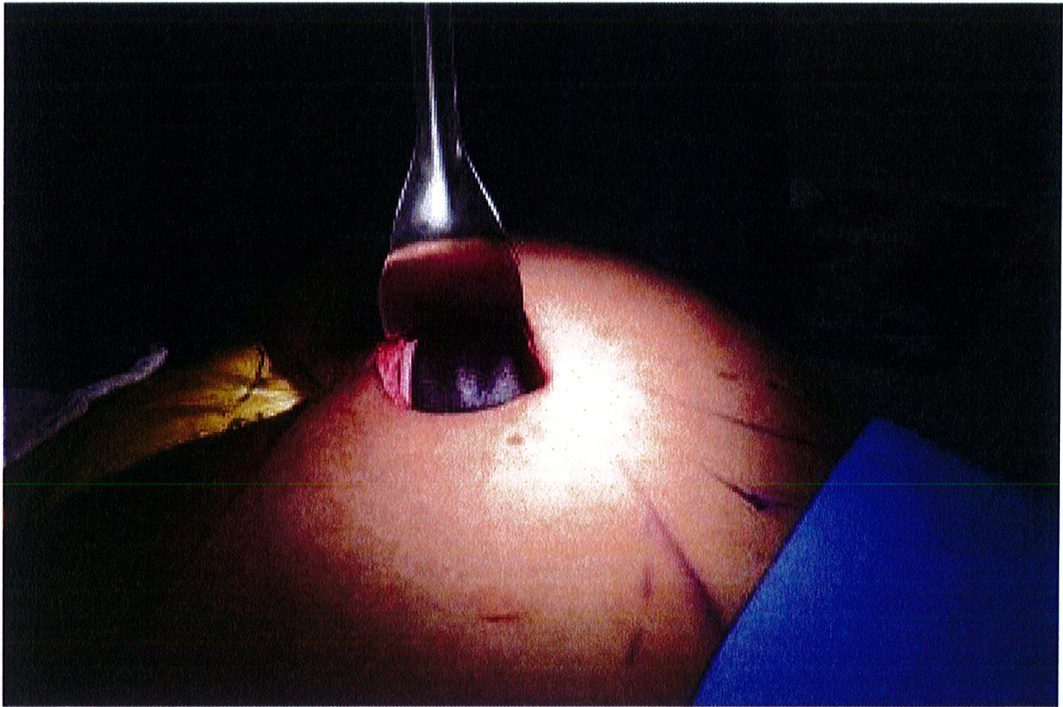

Dụng cụ bóc tách hai đầu tù, hình tròn được sử dụng để phân tách mặt phẳng vô mạch đã được bộc lộ bằng cách tiêm dung dịch trước đó, nhằm bảo tồn tối đa vách và lớp cân mạc. Nên thực hiện bóc tách từ trong ra ngoài, từ trên xuống dưới với một dụng cụ banh có đèn sợi quang (Hình 10). Để tách các vách ngăn, sử dụng một cây bóc tách dài có một đầu nhọn hoặc kéo dài (Hình 11). Các nhánh động mạch mông trên, mông dưới và một số mạch nuôi cho vùng cân mạc được đốt điện. Hãy chắc chắn

Hình. 9. Đánh dấu các mốc giải phẫu quan trọng. (A) Đường rạch cân cơ mông lớn bắt đầu từ bờ ngoài xương cùng (B) Bắt đầu bóc tách lớp cân từ đường rạch ban đầu (Trích từ de la Pena JA, Rubio OV, Cano JP, et al. Subfascial Gluteal aug- mentation. Clin Plast Surg 2006;33:411; đã xin phép trước khi đăng tải.)